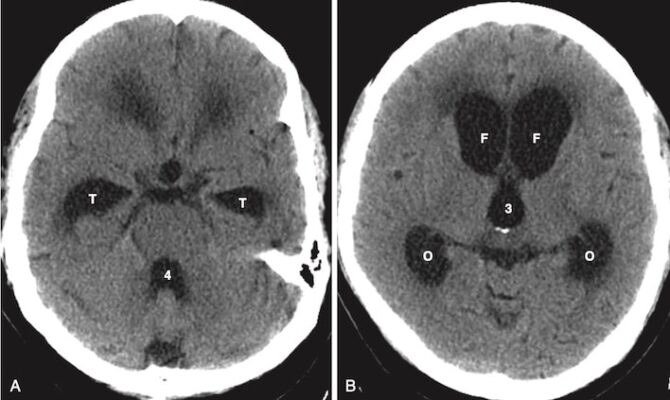

NÃO ÚNG THỦY (HYDROCEPHALUS)

- Não úng thủy được định nghĩa là sự giãn nở của hệ thống não thất trên cơ sở tăng thể tích dịch não tủy chứa trong nó (Hộp 3).

- Trong não úng thủy, các não thất thường bị giãn rộng một cách không cân đối so với với rãnh não, trong khi trong teo não thì cả não thất và rãnh não đều giãn rộng.

- Sừng thái dương đặc biệt nhạy với tăng áp lực dịch não tủy. Trong trường hợp không có não úng thủy, sừng thái dương hầu như không nhìn thấy được. Với não úng thủy, sừng thái dương có thể có kích thước lớn hơn 2 mm (Hình 22).

Não úng thủy do tắc nghẽn

- Não úng thuỷ tắc nghẽn được chia thành hai loại chính: thông (tắc nghẽn ngoài não thất) và không thông (tắc nghẽn trong não thất).

- Não úng thủy thông (communicating hydrocephalus) là do các bất thường ức chế tái hấp thu dịch não tủy, thường xảy ra ở nhung mao màng nhện (Hình 23).

- Bình thường dòng chảy dịch não tủy qua các não thất và nền sọ không bị cản trở. Sự tái hấp thu qua nhung mao có thể bị hạn chế bởi những nguyên nhân như xuất huyết dưới nhện hoặc viêm

- màng não.

- Điển hình, não thất 4 bị giãn ra trong não úng thủy thông và có kích thước bình thường trong não úng thủy thông.

- Não úng thủy thông thường được điều trị bằng đặt shunt não thất.

- Não úng thủy không thông xảy ra do các khối u, nang hoặc các tổn thương gây tắc nghẽn khác không cho dịch não tủy thoát ra khỏi các não thất (Hình 24).

- Não úng thủy bẩm sinh thường được tạo ra do tắc nghẽn giữa não thất 3 và não thất 4 ở cống Sylvius (tắc nghẽn cống).

Não úng thủy áp lực bình thường (Normal-Pressure Hydrocephalus)

- Não úng thuỷ áp lực bình thường (NPH) là một dạng não úng thủy thông được đặc trưng bởi tam chứng lâm sàng cổ điển: bất thường về dáng đi, sa sút trí tuệ và tiểu không tự chủ. Tuổi khởi phát thường từ 60 đến 70 tuổi.

- Việc nhận biết loại não úng thuỷ này rất quan trọng vì thường có thể điều trị được bằng sử dụng shunt não thất – phúc mạc một chiều, cho phép dịch não tủy thoát ra khỏi não thất và dẫn lưu vào khoang màng bụng, nơi dịch não tủy được tái hấp thu.

- Các dấu hiệu về hình ảnh học cũng tương tự như các dạng não úng thủy thông khác và gồm giãn não thất, đặc biệt là sừng thái dương, với các rãnh não bình thường hoặc dẹt (Hình 25).

TEO NÃO (CEREBRAL ATROPHY)

- Các rối loạn liên quan đến teo não đại thể cũng liên quan đến chứng sa sút trí tuệ (dementia), mà bệnh Alzheimer là một trong những bệnh phổ biến nhất. Teo có nghĩa là mất cả chất xám và chất trắng.

- Phát hiện chính ở bệnh nhân mắc bệnh Alzheimer (mặc dù không đặc hiệu) là teo vỏ não lan tỏa, đặc biệt là ở thùy thái dương.

- Giống như trong não úng thủy, các não thất giãn ra trong bệnh teo não, nhưng là do mất mô não bình thường tạo ra một khoảng trống được lấp đầy thụ động bởi các não thất chứa đầy dịch não tủy. Không giống như não úng thủy, sản xuất và hấp thụ dịch não tủy là bình thường trong teo não.

- Nói chung, teo não dẫn đến sự to ra tương xứng của cả não thất và các rãnh não (Hình 26).